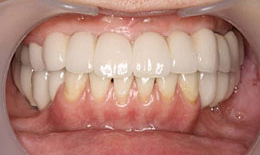

インプラント症例(1)30代 女性

治療後

上顎

保存困難な歯を抜歯後、インプラントを7本埋め込み、セラミックスクラウンを被せた

下顎

保存困難な歯を抜歯後、インプラントを6本埋め込み、セラミックスクラウンを被せた

インプラント

フィクスチャー13本

285,000×13=3,705,000円(税抜)

上部構造

(メタルボンドクラウン)18本

155,000×18=2,790,000円(税抜)

右上

メタルボンドブリッジ

90,000×4=360,000円(税抜)